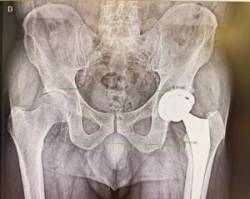

Imagen en alta resolución. Este enlace se abrirá mediante lightbox, puede haber un cambio de contextoLa llamada vía anterior en la prótesis de cadera no es una técnica nueva, aunque en los últimos años ha ganado popularidad. A diferencia de otros abordajes, permite acceder a la articulación entre planos musculares, sin necesidad de cortar músculos, lo que se traduce en un postoperatorio inmediato más rápido.

"La gran ventaja de la vía anterior es que el paciente tiene menos dolor en los primeros momentos tras la cirugía y puede iniciar antes la movilización", explica el Dr. Martín Buenadicha. A medio plazo, los resultados funcionales tienden a equipararse con otras vías, pero esta recuperación inicial más ágil resulta especialmente relevante cuando se plantea un alta precoz.